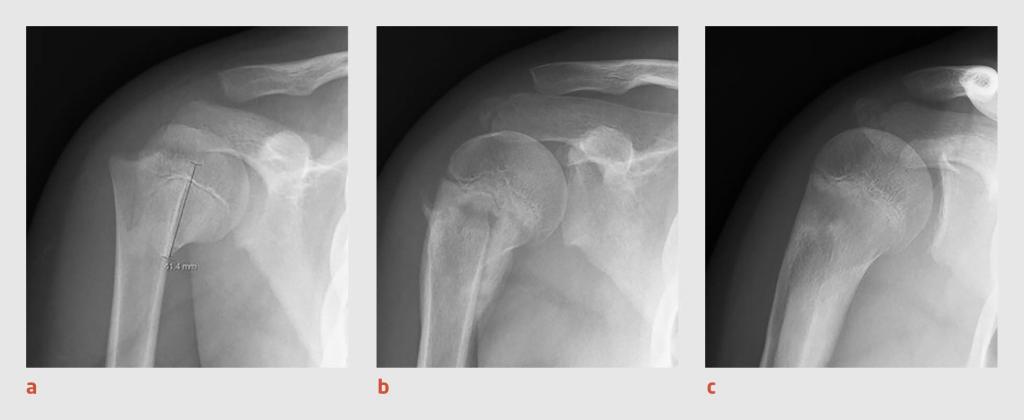

Figuur 4 | Remodellering van de proximale humerus na een fractuur bij een 13-jarige jongen

Röntgenfoto’s van de rechter schouder van patiënt B, (a) 10 dagen, (b) 10 weken en (c) 8 maanden na de humerusfractuur. De foto’s tonen goede consolidatie en remodellering van de proximale humerus.